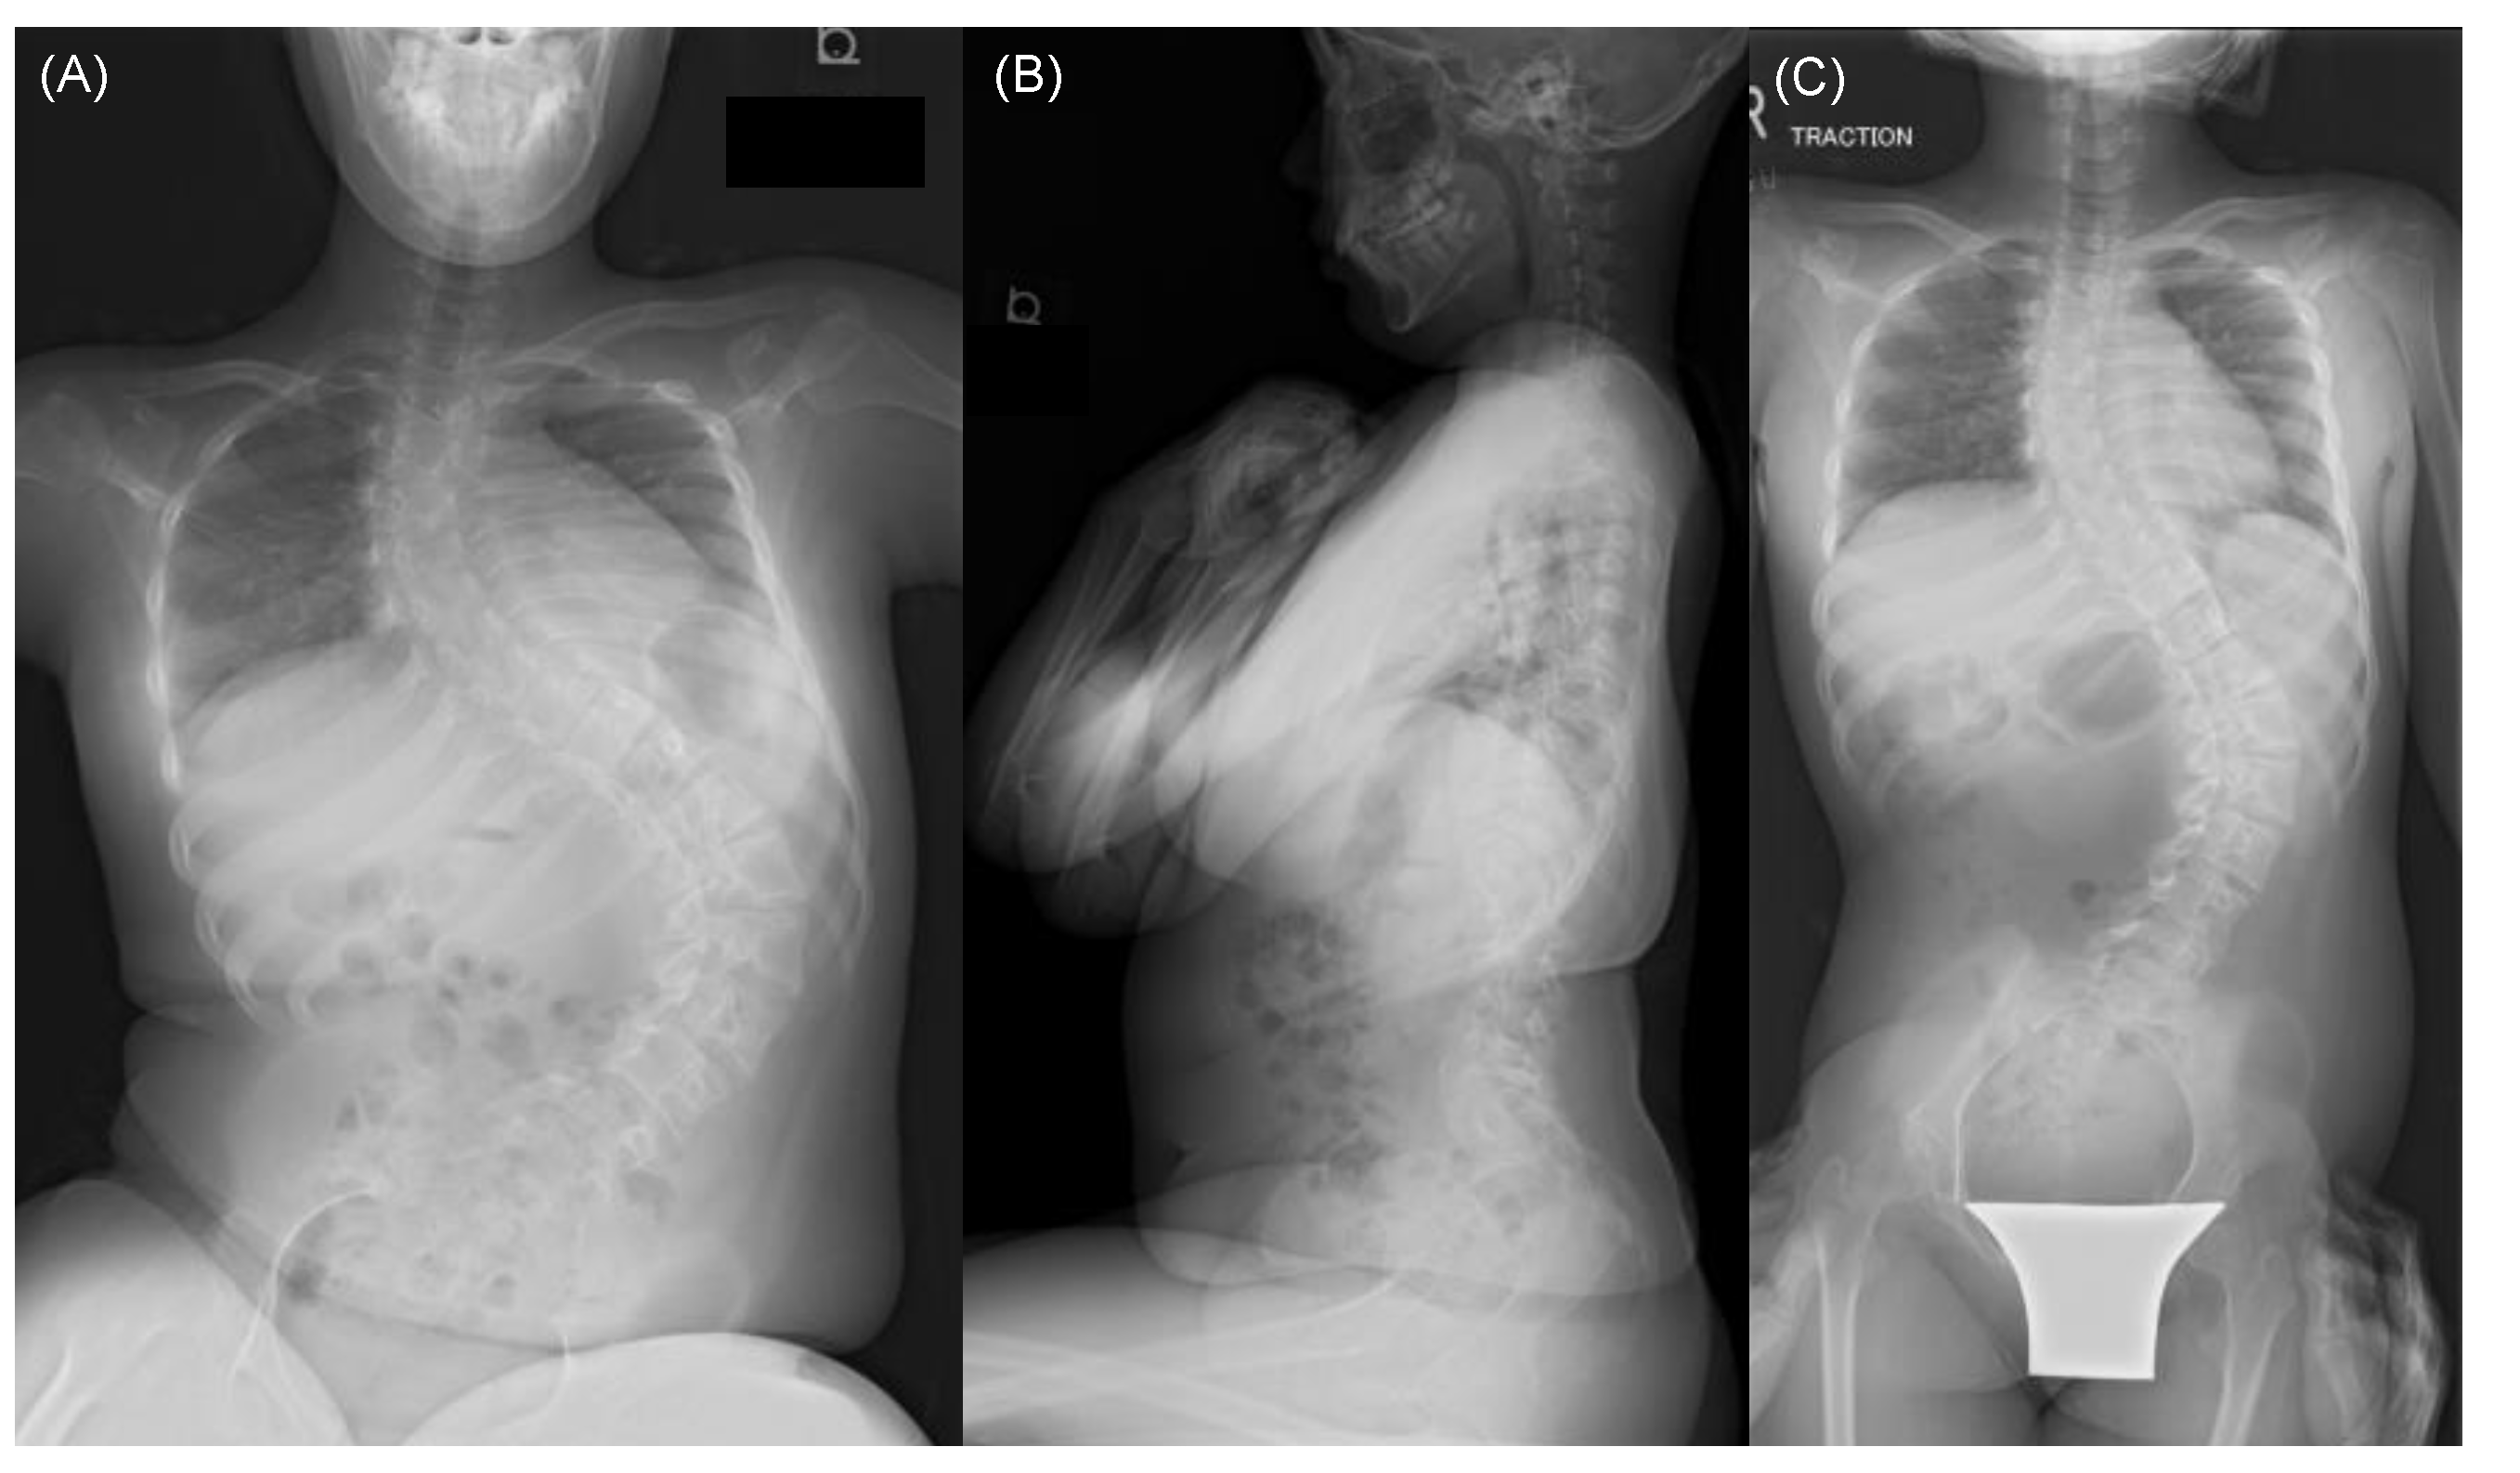

Representative Case Presentation